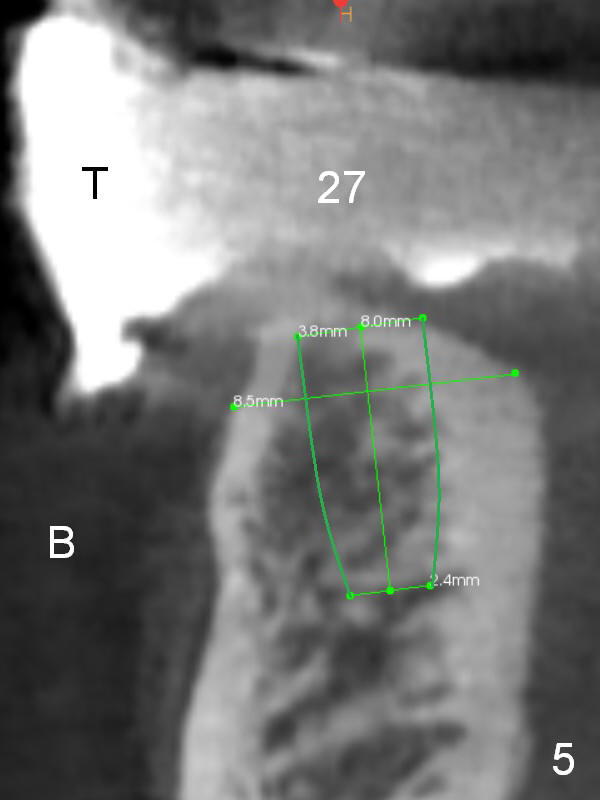

The patient wants to change unstable complete dentures to fixed ones.  Because the problem of pain is associated with the lower left (Fig.1 the left Inferior Alveolar Nerve is more superficial), the lower arch will be reconstructed first.  Totally 6 implants will be placed for bridges/crowns.  Due to time constraint, four implants are placed at the 1st stage (#21, 22, 27 and 28 (Fig.4,5,8,9)); the lower denture will be retained immediately by ball abutments and soft relined.  Two to three months later, two more implants will be placed (at #31 and 20, Fig.2,10).  Note severe atrophy of the crest at #18 and 19 (Fig.11 and 12).  If primary stability is achieved, a fixed immediate provisional will be fabricated.

In contrast to the upper arch, the bone density in the lower arch is high.  The challenge is bone height.  Short implants will be used (6 mm for #31 (Fig.2) and 8 mm for the majority of the others (at premolar and canine sites).  If needed, extra implants will be placed at incisor sites (Fig.6,7 (implant can be longer)) and at #29 (Fig.3) .  If a site is too small for a 3.8 mm 2-piece implant, a 1-piece one may be placed.